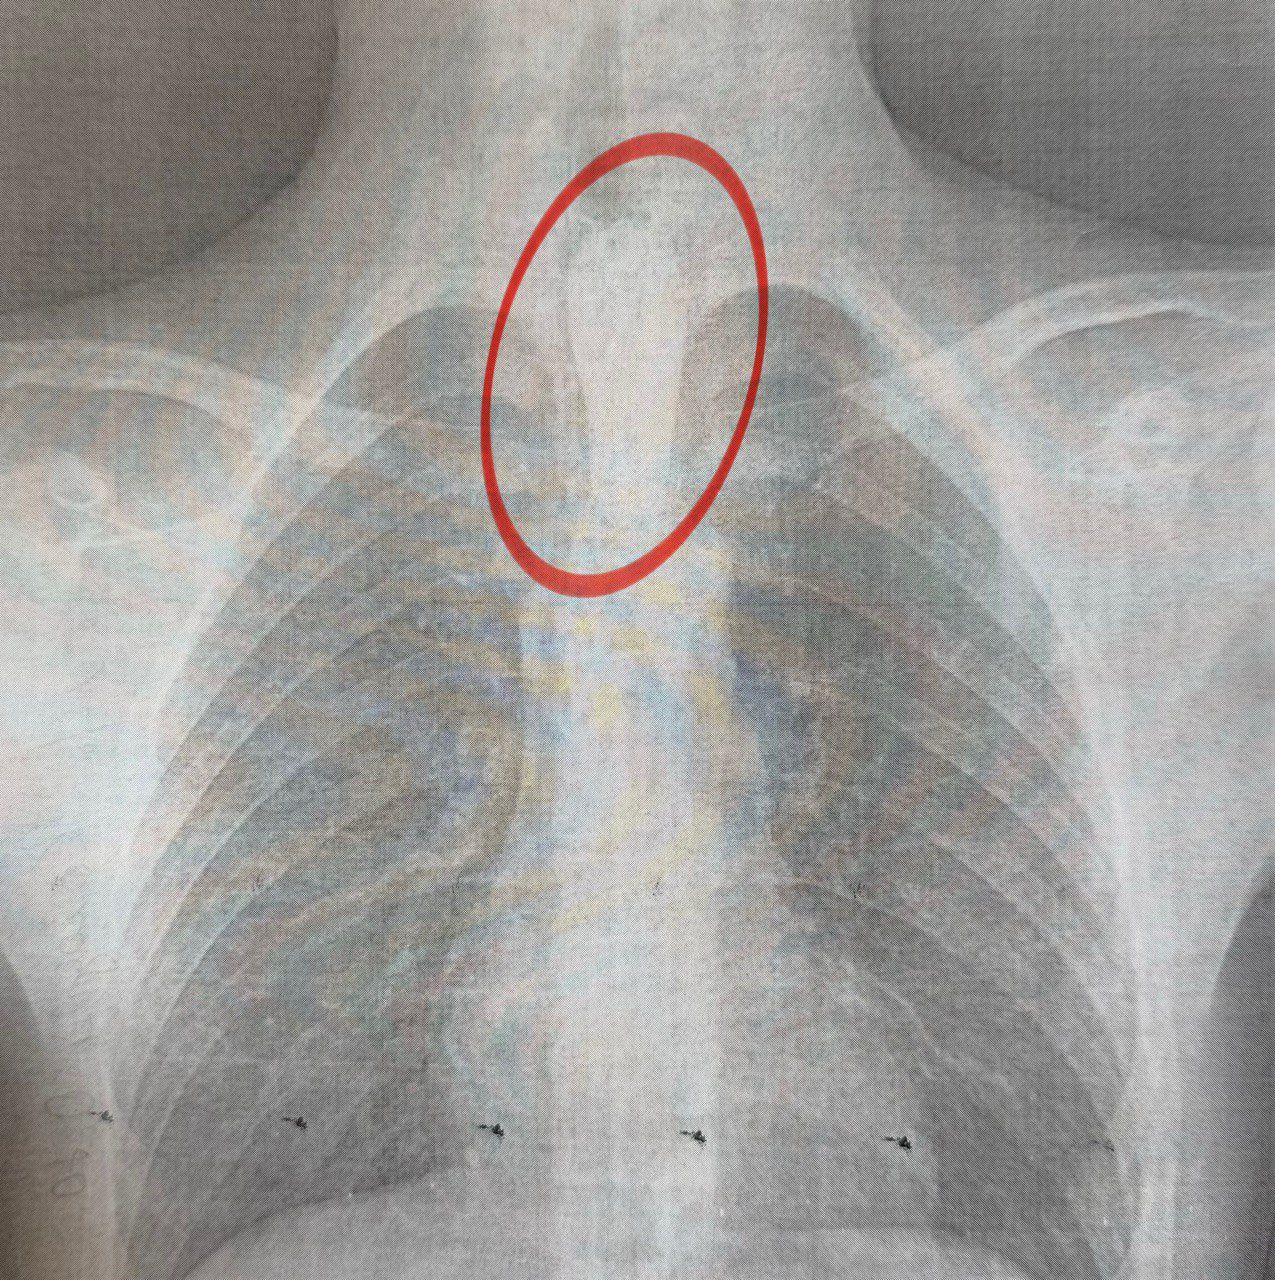

Як розповів торакальний хірург Олександр Колодій, шматок м'яса зупинився на одному з природних звужень стравоходу — біля аорти, що значно ускладнило ситуацію.